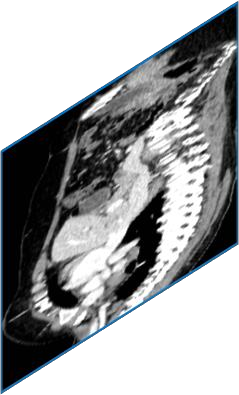

Due to the constraints of the imaging device and high cost in operation time, computer tomography (CT) scans are usually acquired with low intra-slice resolution. Improving the intra-slice resolution is beneficial to the disease diagnosis for both human experts and computer-aided systems. To this end, this paper builds a novel medical slice synthesis to increase the between-slice resolution. Considering that the ground-truth intermediate medical slices are always absent in clinical practice, we introduce the incremental cross-view mutual distillation strategy to accomplish this task in the self-supervised learning manner. Specifically, we model this problem from three different views: slice-wise interpolation from axial view and pixel-wise interpolation from coronal and sagittal views. Under this circumstance, the models learned from different views can distill valuable knowledge to guide the learning processes of each other. We can repeat this process to make the models synthesize intermediate slice data with increasing inter-slice resolution. To demonstrate the effectiveness of the proposed approach, we conduct comprehensive experiments on a large-scale CT dataset. Quantitative and qualitative comparison results show that our method outperforms state-of-the-art algorithms by clear margins.